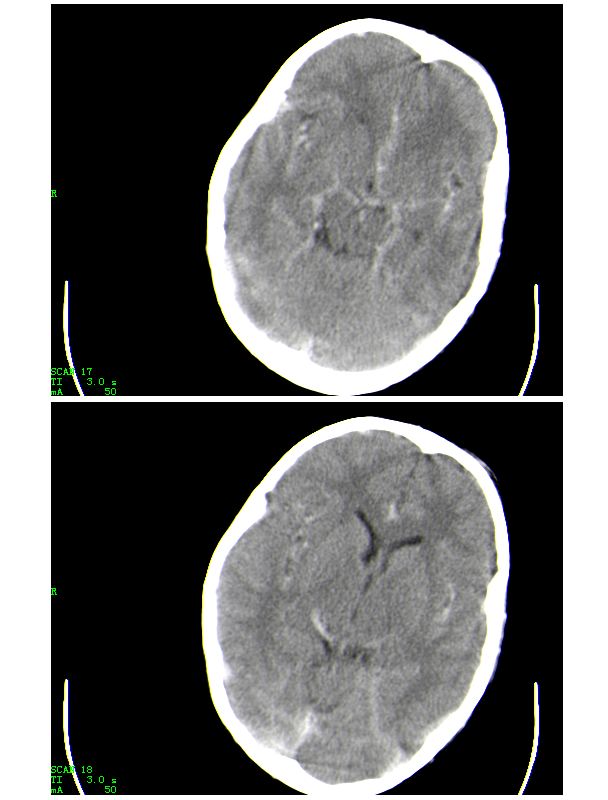

男,13岁,头部外伤后头痛、呕吐三小时就诊,查体,见小孩精神状态尚可,面部,嘴唇青紫明显,后作心脏彩超证实为“发四”,有复查片,大家先看看首诊片,考虑什么

感谢大家的关注,本例我们最后诊断为高血红蛋白症所致的脑血管改变,患者血红蛋白258g/l

下面是第二天的复查和受伤后第五天的复查,左侧硬膜下血肿有所吸收,脑内条状高密度无改变